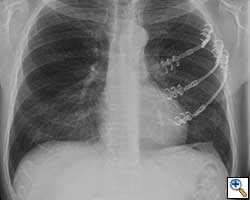

- Chest wall resection for malignancy (Figures 4-5)

![]() |

| Figure 4: Model showing application in chest wall resection. | Figure 5: Postoperative chest x-ray showing the implants |

Here we present, as a paradigm of repair, the case of a 65 year old gentleman referred to our institution for an indolent mass in the left anterior chest wall. Repairs for other conditions follow the same rules. This mass had been stable in size for more than 12 months and the patient was prompted to seek medical attention as, after weight loss due to dieting, he felt the mass was uncomfortable while sleeping. Apart from coronary stenting for angina, the past medical history was unremarkable.

Computed tomography scan of the chest showed a mass protruding from the cortex of the third rib. A percutaneous core biopsy was non-diagnostic. We proceeded to an open incisional biopsy. This was reported as showing a spindle cell neoplasm. The patient was therefore scheduled, after multidisciplinary meeting discussion, for radical surgery.

At surgery, the mass was arising from the cortex of the third rib, and solid measuring 5x8 cm. There was no macroscopic involvement of the surrounding extra-thoracic musculature or of the underlying lung, the mass being confined to the rib and intercostal muscles. The patient underwent resection of the second to fourth ribs and the rhomboid muscle as well, in the attempt to get clear margin. The large antero-lateral defect was eventually reconstructed using 2 mouldable titanium bars. To prevent lung herniation through the defect, we reconstructed the layers anatomically using a biological patch (Veritas®). The final histopathology was a low grade sarcoma of the chest wall with clear resection margins.

He made an excellent recovery with daily physiotherapy to encourage shoulder movements. He was discharged with oral analgesia on postoperative day 4. At 1-month follow-up the patient had no pain at all, discontinued analgesia on postoperative day 17 and demonstrated a full range of shoulder movement. His chest x-ray was unremarkable and the wound healed without complication.